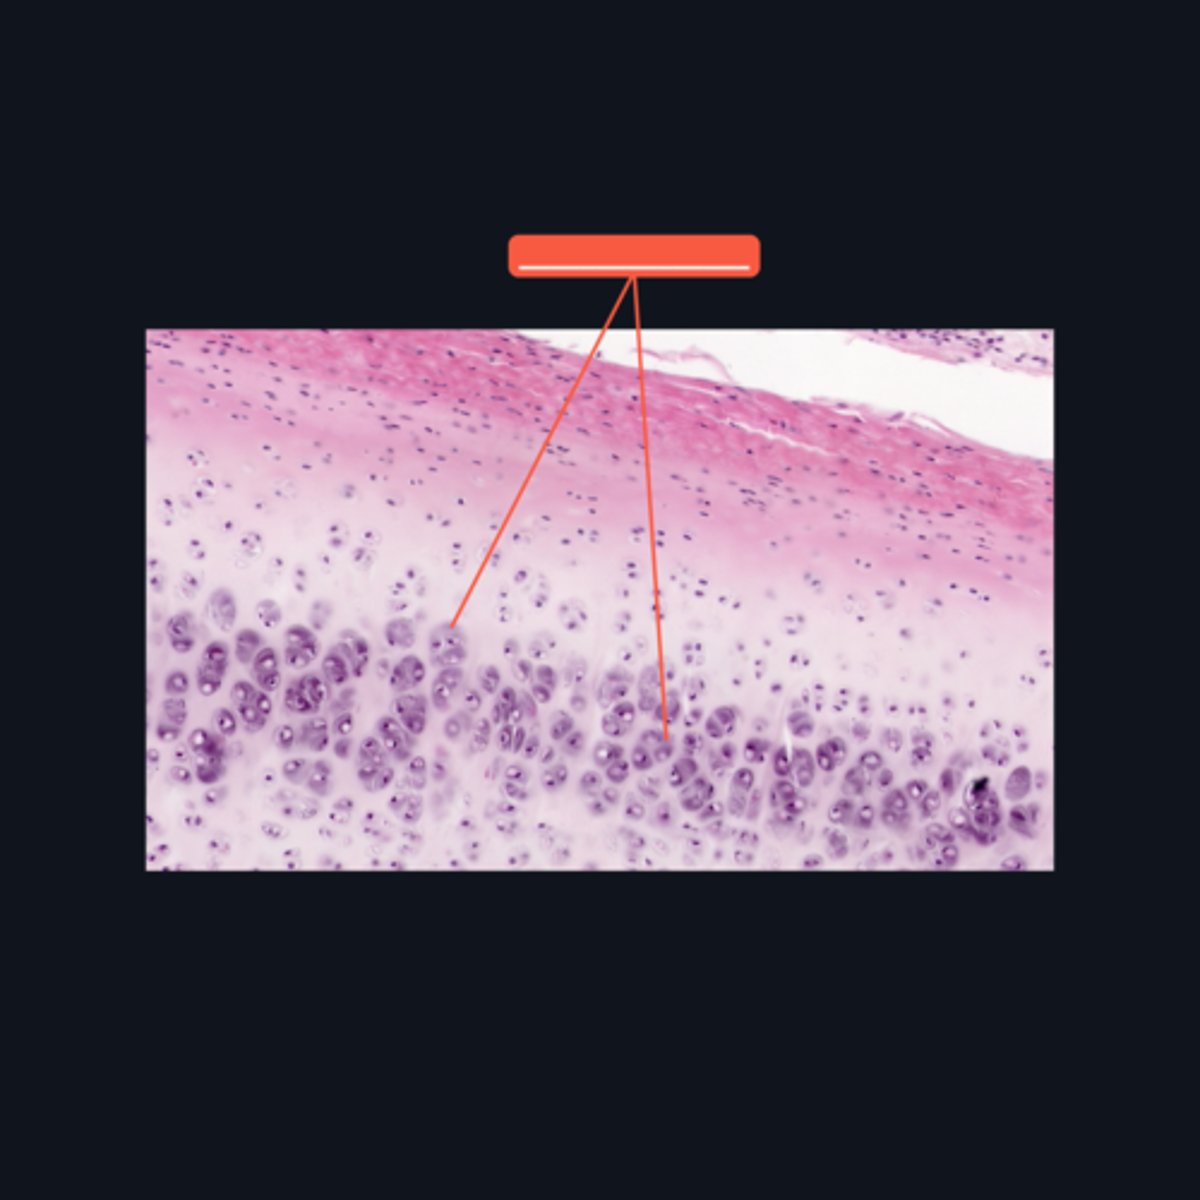

Elastic Cartilage

What type of cartilage is found in the auditory tube and epiglottis?

Type II Collagen

What type of extracellular fibers make up the elastic cartilage?

Black Streaks

When stained with orcein, elastic fibers characteristically appear like _____ in the matrix.